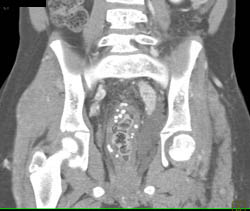

Diagnosis

Open Reduction Internal Fixation (ORIF) of Tibial Fracture